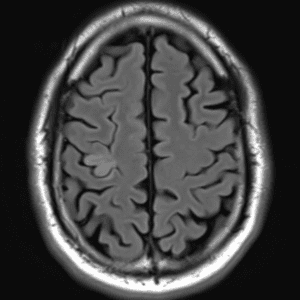

Brain Tumor Practice Cases

Case #4

Focal cortical dysplasia (type II)